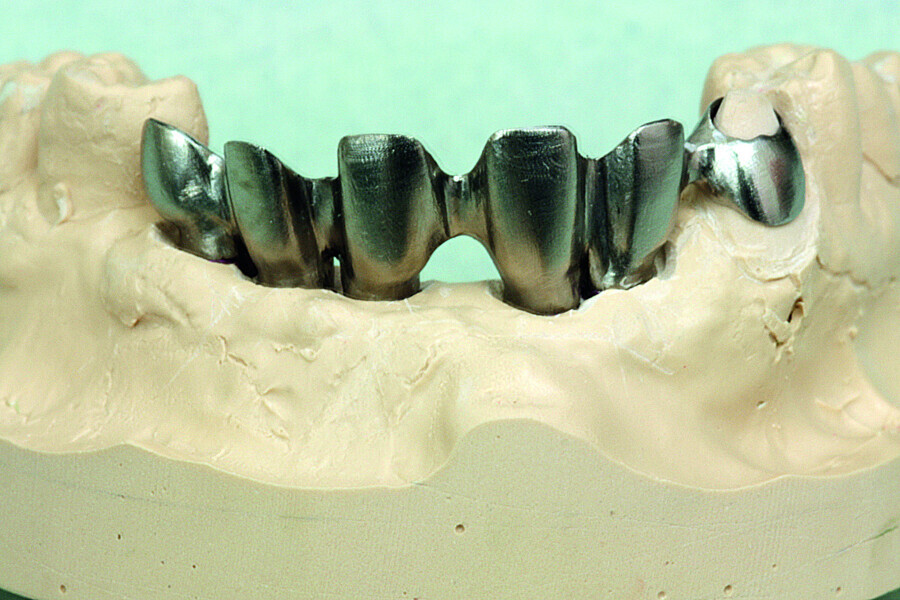

Fig. 32: Final prosthesis framework and the coping for the right canine tested on the working model.

Fig. 33: Final prosthesis framework and the coping for the right canine tested on the working model.